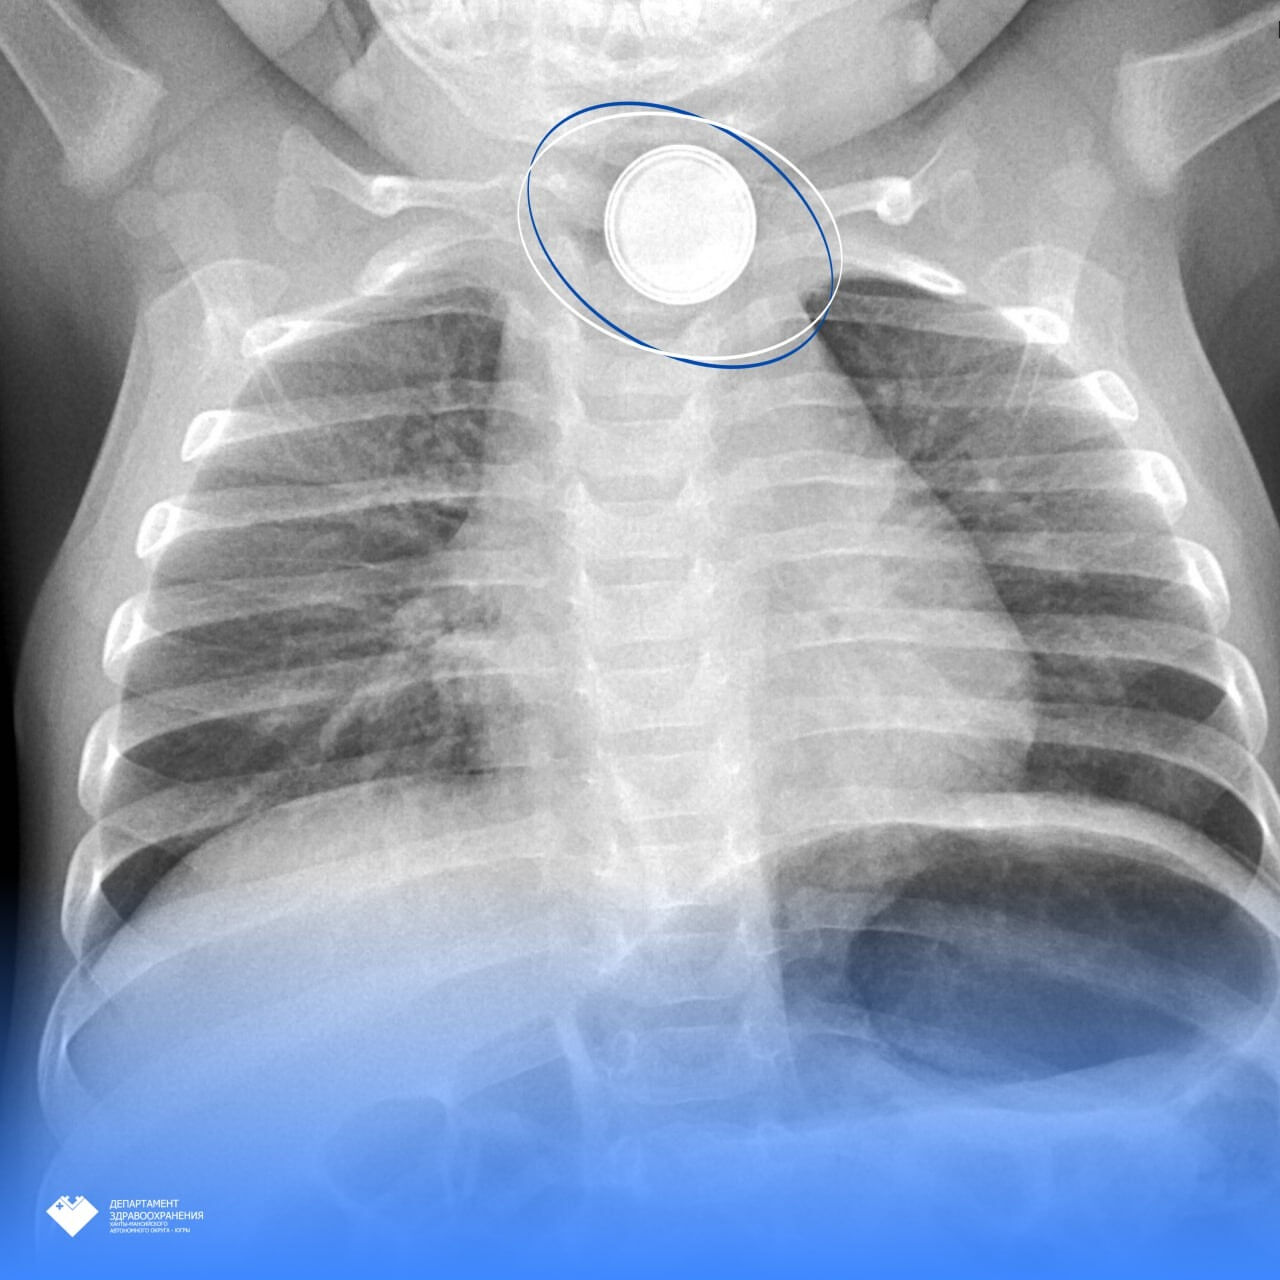

Как рассказали в пресс-службе Здравоохранения Югры, в Нефтеюганскую районную больницу на скорой привезли 11-месячного малыша. Родители заподозрили, что ребенок проглотил опасный предмет и решили вызвать врачей. Рентген подтвердил, что в теле младенца находился инородный предмет, который застрял в верхней части пищевода. Когда врачи об этом узнали, ребенка срочно эвакуировали в Сургут в Центр охраны материнства и детства.

– Там маленький пациент поступил в детское хирургическое отделение №3. Повторное эндоскопическое исследование выявило критическую ситуацию: аккумулятор диаметром 1,5 см вызвал тяжелый электрохимический ожог 3 степени. Было принято решение о срочной операции, – сообщили в пресс-службе.